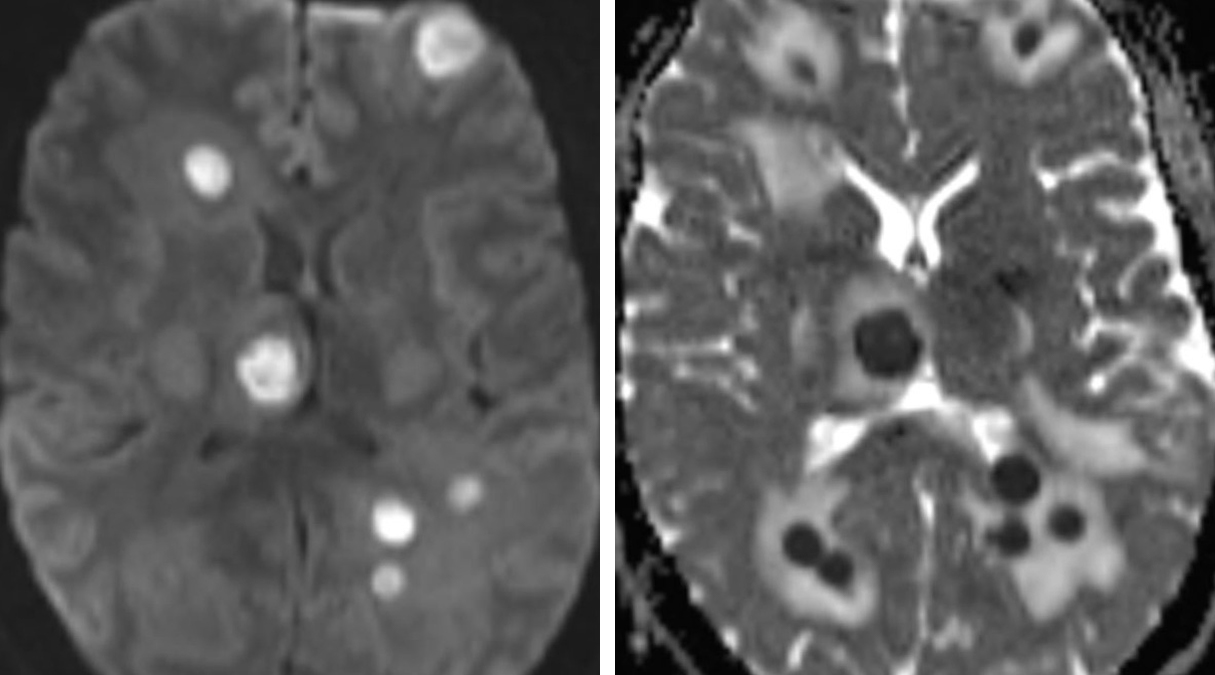

Cerebritis/Abscess | Cohen Collection | Volumes | The Neurosurgical Atlas